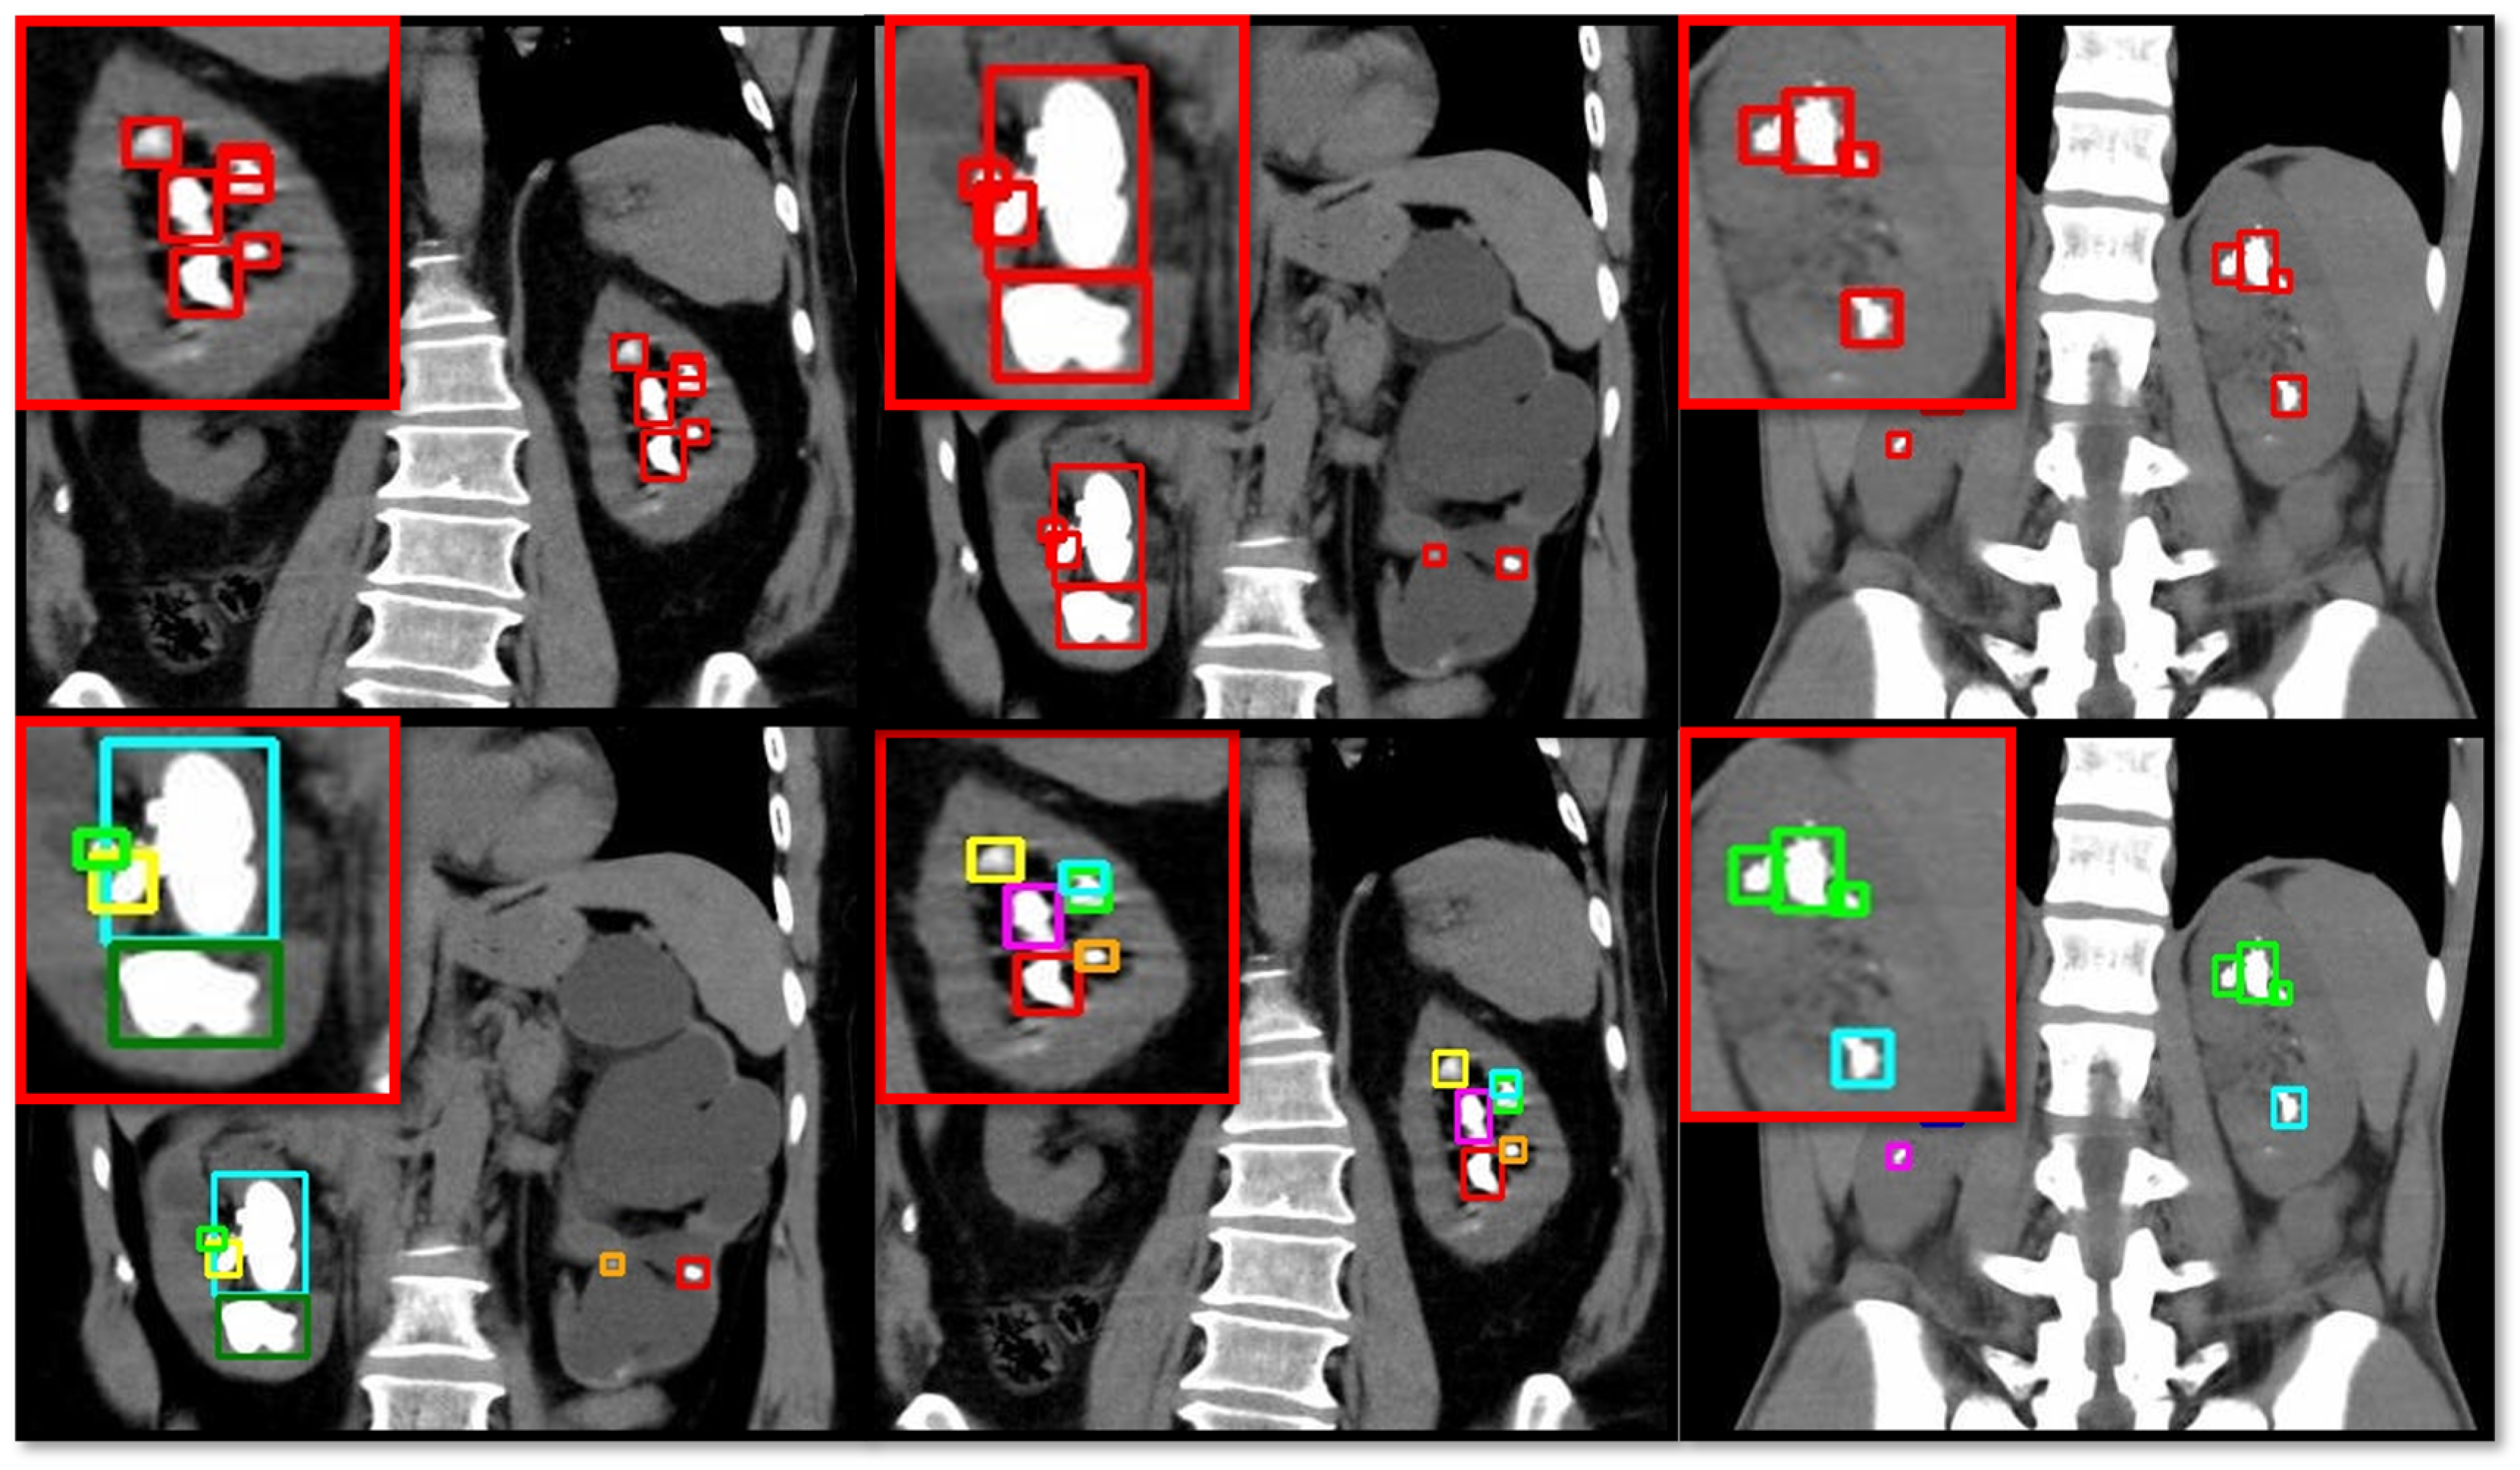

Figure 3 provides a comprehensive visual representation of the results obtained from the kidney stone detection algorithm applied to a series of medical CT scans. The images are arranged in a grid format, where each row represents a different slice or section of the scan and each column shows different views or slices of the same section. The blue bounding box highlights areas where potential stones are detected. They contain the label “stone” followed by a confidence score, indicating the likelihood of the detected object being a kidney stone. These confidence scores, displayed next to the “stone” label (e.g., “stone 0.78”), measure the model’s certainty in its detection. Higher confidence scores signify greater certainty and provide a quick assessment of detection reliability. The first column displays a vertical CT scan of the kidney. Both the YOLOv5n model and the proposed model showed a confidence score of 0.77 (77%) for stone detection. In contrast, the YOLOv5m model demonstrated a significantly lower performance for medical data, with a confidence score near 0.51 (51%). The second and third columns show the upper CT scans of the human kidney, where the models were tasked with detecting the two stones. All models showed high confidence scores; however, the proposed model surpassed YOLOv5s by demonstrating confidence scores of 0.89 (89%) and 0.84 (84%). In the third column, the proposed model again showed superior performance, with a confidence score that was 0.02 higher than that of YOLOv5s, which had a score of 0.84 (84%). The last column shows a partially cropped CT scan of the kidney. Both the YOLOv5n and YOLOv5s models demonstrated identical results, with confidence scores of 0.79 (79%). The proposed model slightly outperformed these two models, with a confidence score that was greater by approximately 0.01. This comparative analysis underscores the enhanced performance of the proposed model in detecting kidney stones and demonstrates its potential for achieving higher accuracy in medical imaging applications.

Figure 3.

Comparative analysis of different YOLOv5 model variants (nano-sized, small, and medium) along with the proposed modified YOLOv5 model for the detection of kidney stones in CT images.